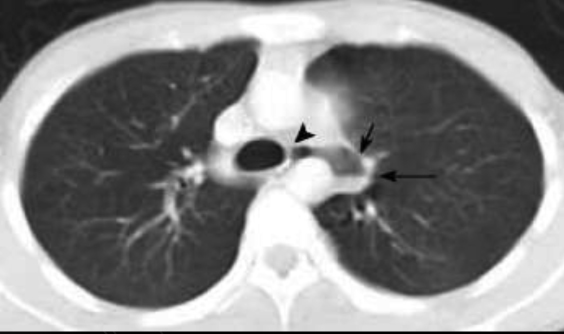

Au niveau du bronche souche

gauche ,oesophage se situe en arriere et avait

un peut serre .A gauche c'est aorte thoracique (

coupe axiale TDM thoracique au desous de bifurcation

tracheale ) . |

Coupe axiale TDM

thoracique au dessus de diapragme . Image si net de

oesophage situe en avant et a droite de aorte

thoracique . |